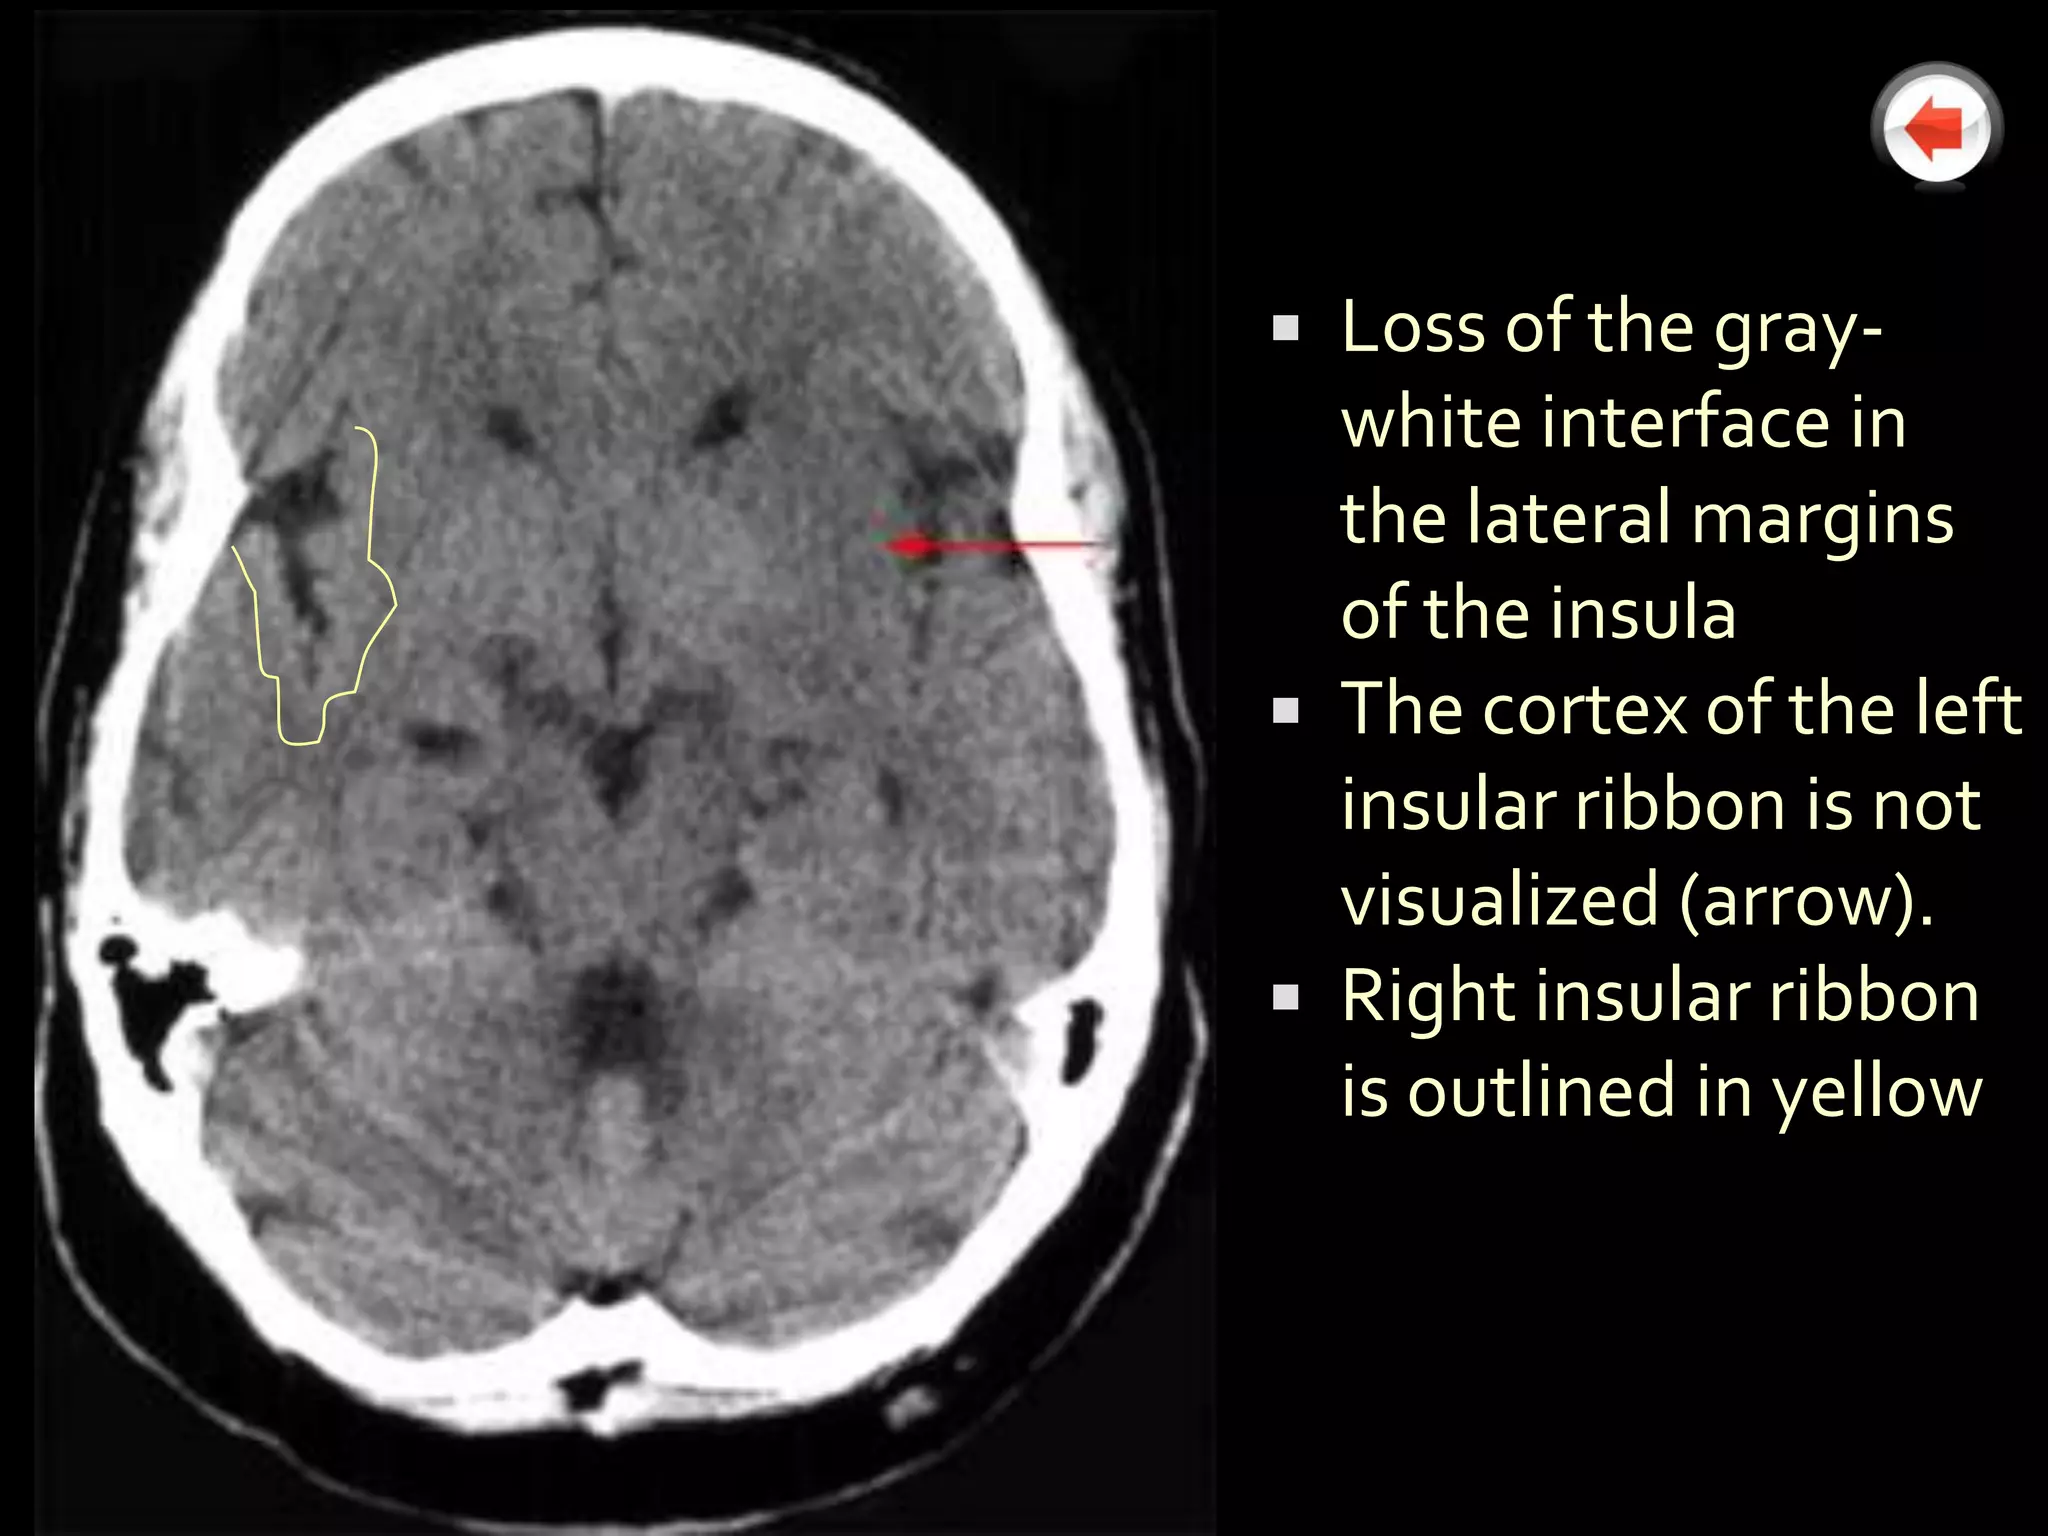

 Loss of the gray-

white interface in

the lateral margins

of the insula

 The cortex of the left

insular ribbon is not

visualized (arrow).

 Right insular ribbon

is outlined in yellow

 Etiologies includethrombus, embolism, or hypoperfusion  Ischemic brain tissue becomes edematous  Edematous tissue will appear hypodense on noncontrast CT  Hypodensity begins as early as 1h post-CVA ▪ Earliest sign of CVA is loss of gray-white differentiation (the "insular ribbon" sign)  Hypodensity is completely manifest by 12-24 hours post- CVA

Obscuration of the lentiform nuclei  Hypoattenuation of the insular ribbon  Sulcal effacement and cortical hypodensity  Hyperdense vessel signs